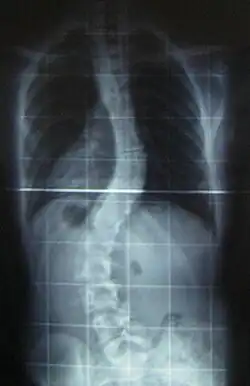

Another form of CMD is rigid spine congenital muscular dystrophy (RSMD1), or rigid spine syndrome, which is caused by mutations in the SELENON gene encoding for selenoprotein N.[13] The exact function of selenoprotein N is unknown, but it is expressed in the rough endoplasmic reticulum of skeletal muscle, heart, brain, lung, and placenta tissues, as well as at high levels in the diaphragm.[13] RSMD1 is characterized by axial and respiratory weakness, spinal rigidity and scoliosis, and muscular atrophy, and while it is a rare form of CMD, SEPN1 mutations are observed in other congenital myopathies.[9]

- CMD with spinal rigidity present at birth can have poor muscle tone and weakness, reduced respiratory capacity, muscles could be deformed, beginning early ages stabilization or slow decline spinal rigidity, limited mobility to flex the neck and spine, spinal curvature and progressing deformity and rigidity joints, minor cardiac abnormalities, normal intelligence.[26]